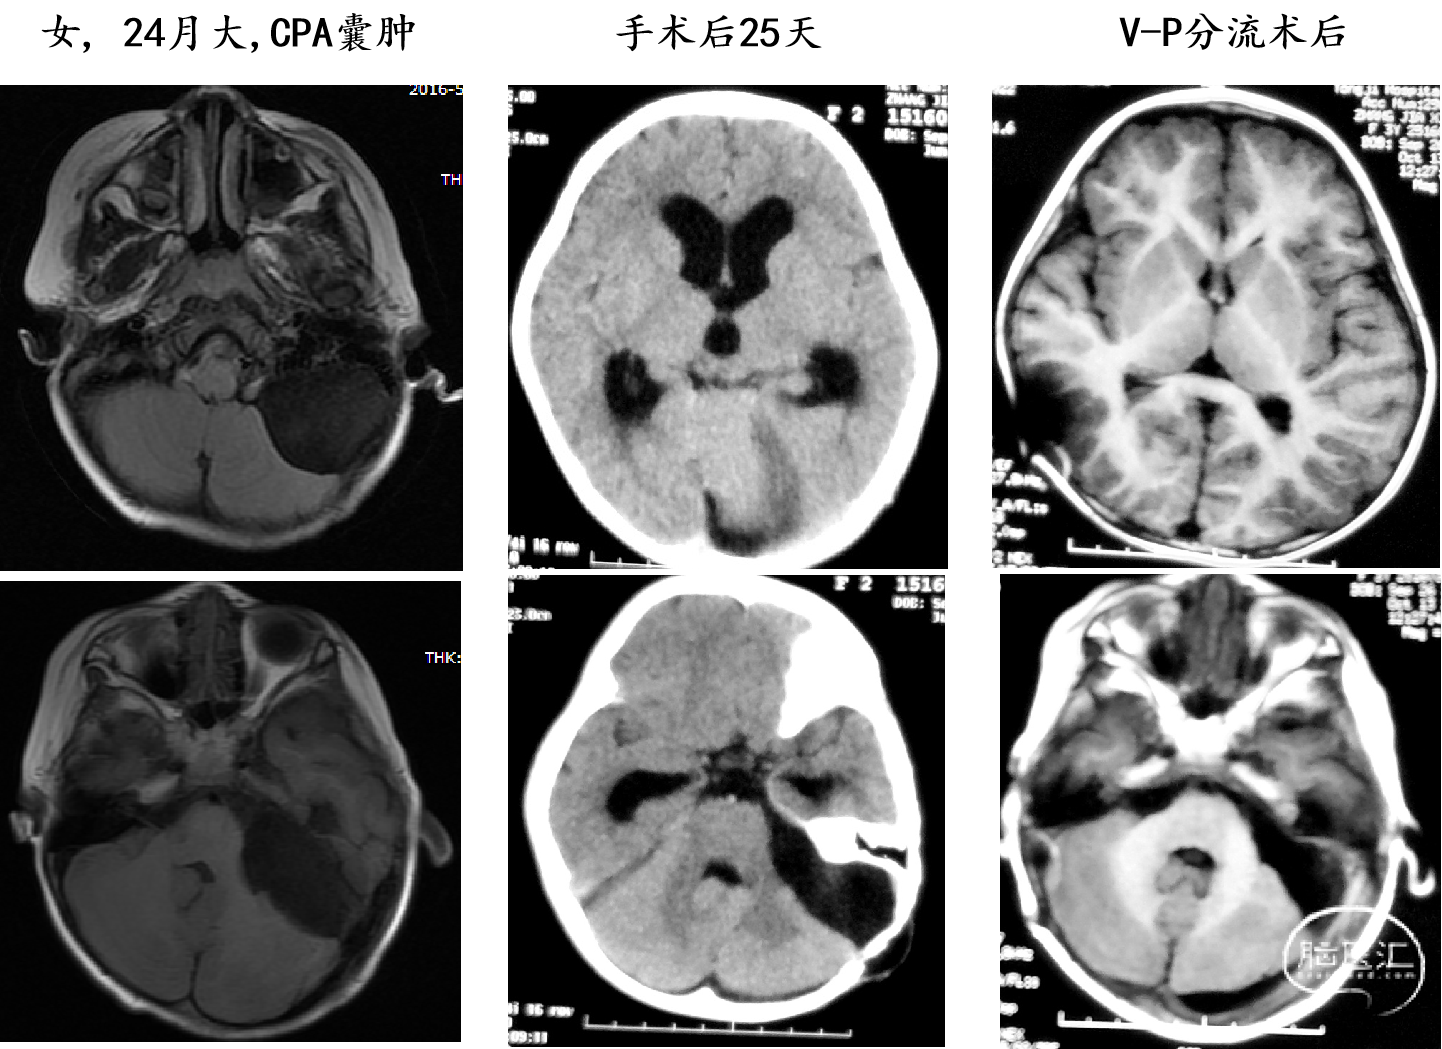

2岁以下囊肿切除/造瘘术后出现积液(Hg)/积水(Hc)

囊肿切除术后出现积液/积水

婴儿巨大囊肿:我们建议囊肿腹腔分流术(可调压分流管)需密切随访分流管依赖综合征可能